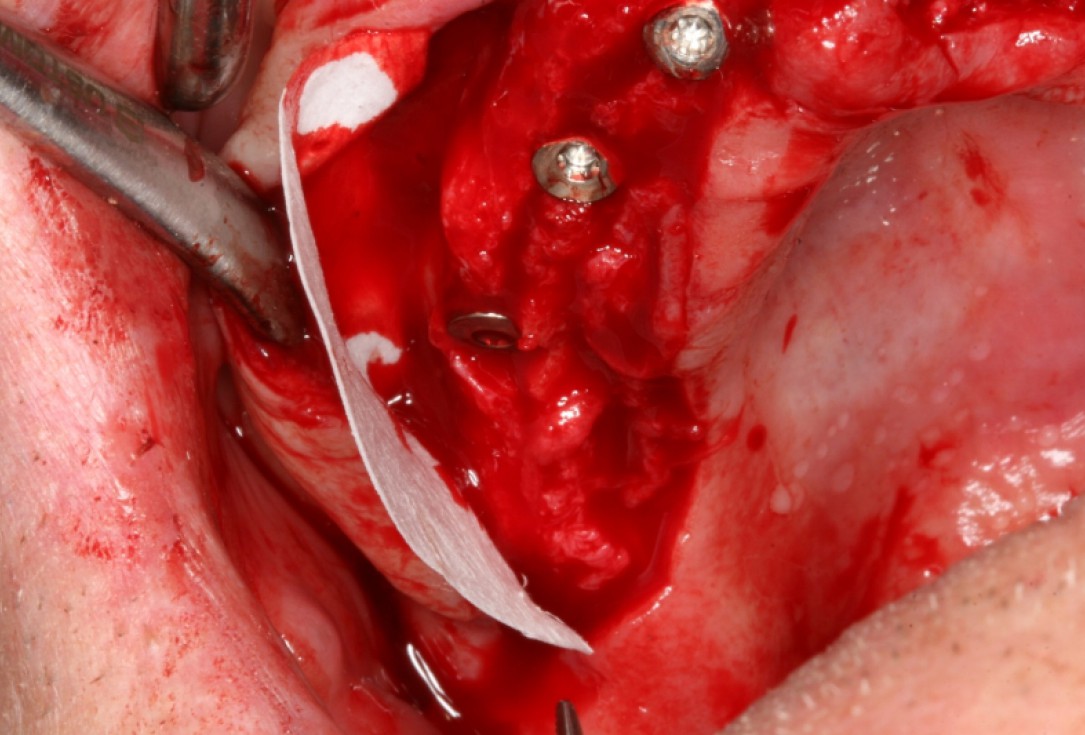

03/10 - Positioning of collprotect® membrane for application of bone graft materialCircular bone splitting with maxresorb® & collprotect® membrane - PD Dr. J. Neugebauer